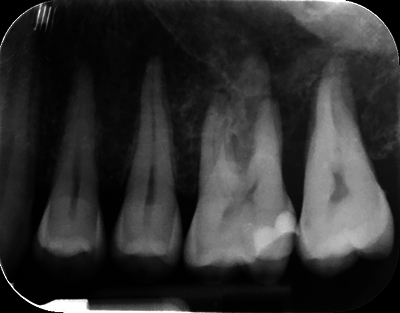

一名 47 岁的男性病史并无异常,因左上磨牙的非典型牙髓疼痛和治疗而转诊。临床和影像学检查发现,这些牙齿周围有一个广泛的、未定义的溶骨区。随后的骨活检诊断为弥漫大 B 细胞淋巴瘤,这是一种高级别非霍奇金淋巴瘤。血液科团队开出了六个周期的化疗处方,并辅以两个周期的甲氨蝶呤。医生应警惕非典型牙痛,考虑进行三维成像检查,以尽早排除恶性病变。教学要点:非典型牙痛应引起医生的警觉,并引导他们进行三维成像检查,以尽早排除恶性病变的诊断。

A 47-year-old male with an unremarkable medical history was referred for atypical endodontic pain and treatment of his left upper molars. Clinical and radiographic examinations revealed an extensive, undefined osteolytic area around these teeth. A subsequent bone biopsy diagnosed diffuse large B-cell lymphoma, a high-grade non-Hodgkin's lymphoma. The hematology team prescribed six cycles of chemotherapy, supplemented by two cycles of methotrexate. Practitioners should be alerted by atypical tooth pain to consider 3D imaging to exclude malignant pathology as early as possible. Teaching point: An atypical tooth pain should alert the practitioner and guide them towards 3D imaging to eliminate diagnostic of malignant pathology as early as possible.